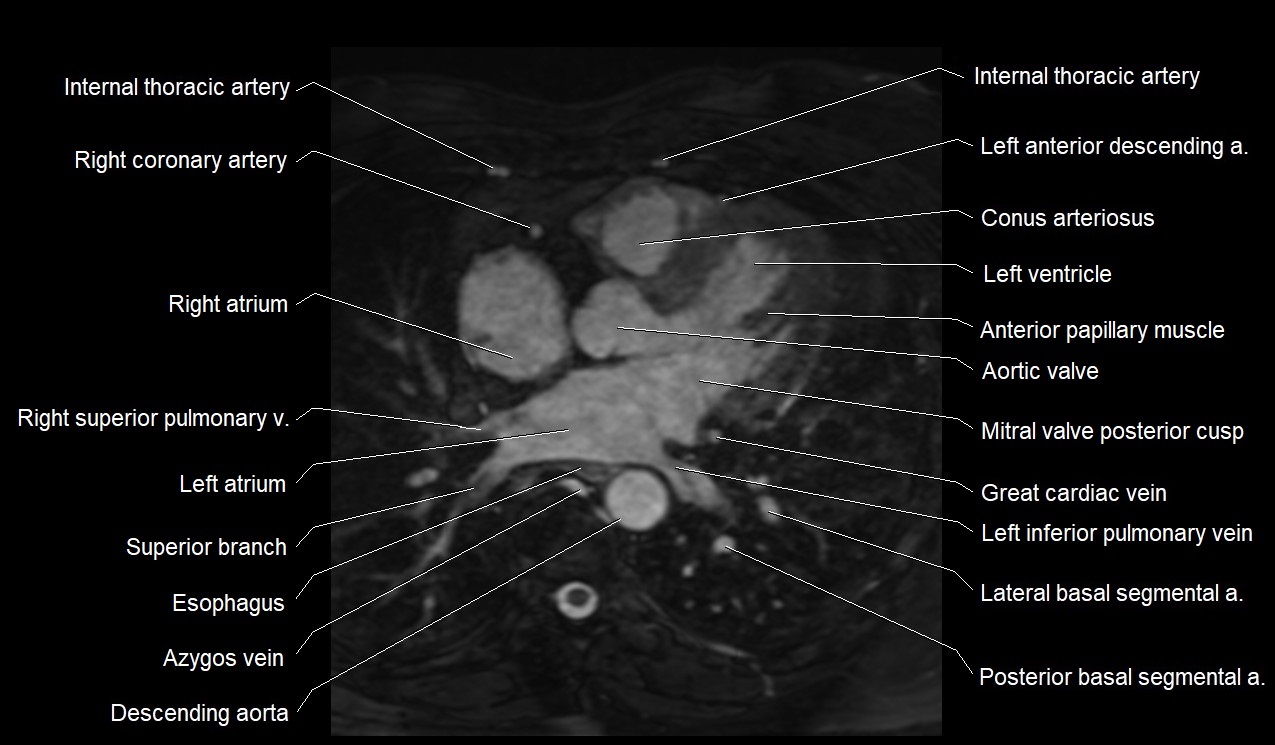

MRI image